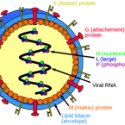

Creating and Testing Vaccines

02/15/21 The amazing mechanisms by which viruses infect cells and the challenge of developing effective vaccines. Forian Douam

Spillover! Virus Transmission from Animals-to-Humans

07/14/21 Many viruses, including coronaviruses such as covid-19, originate in wild animals. Understanding the transfer and infection process is a major concern in medical science today. Jonathan Runstadler

Understanding Viruses: The Connor Lab

07/2014 The Connor Lab at Boston University is a leader in the effort to understand how viruses infect and how cells learn how to block infection. John Connor

Unraveling the Secrets of Viruses

05/17/11 Why are viruses so successful, and can we manage the bad ones? John Connor

Virus vs Host: An Enduring Battle

02/14/23 Viruses must appropriate the DNA/RNA of living cells in order to survive. The battle between viruses and cell defenses is a classic example of the epic struggles that characterize Nature. John Connor

Viruses: Threats in a Tiny Package

11/06/14 Viral infections that were once obscure are potentially global threats in a highly linked world. New tools are being deployed to identify and block these diseases. John Connor